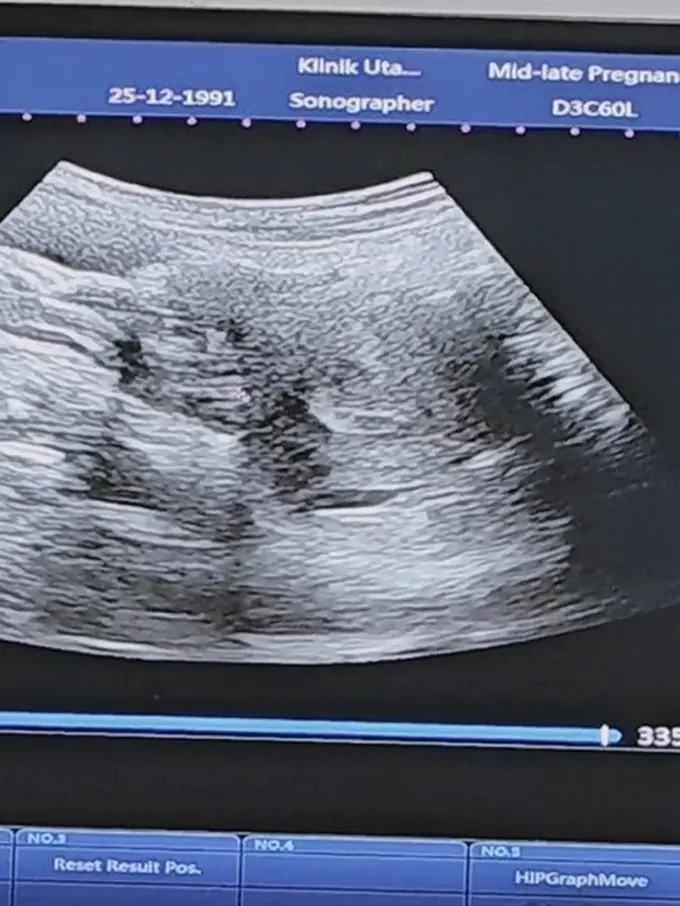

Periksa ke Dokter Kandungan

Dude Harlino turut serta mengantar dan menemani Alyssa Soebandono ke dokter kandungan untuk melakukan pemeriksaan calon anak ketiga mereka, yang berjarak 8 dan 6 tahun dari kakak-kakaknya.

Anak Ketiga

Mereka secara rutin mengunjungi dokter kandungan untuk memeriksa dan memastikan bahwa calon anak ketiga mereka dan Alyssa Soebandono selalu dalam kondisi sehat.